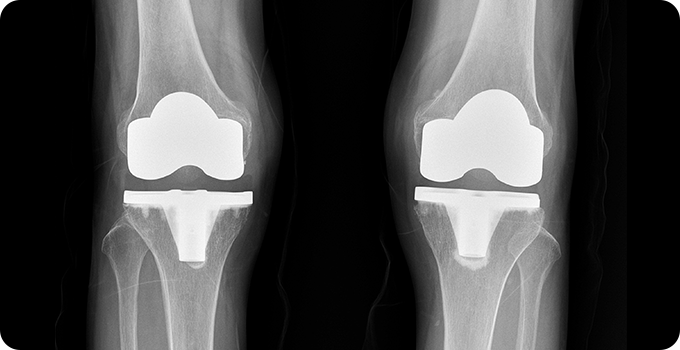

인공관절 수술 치료 사진

4

말기 - 인공관절 수술

손상된 관절을 제거하고 인공 관절로 대체하여 통증을 완화하고 관절 기능을 회복하는 치료법입니다. 이 수술은 주로 말기 퇴행성 관절염 환자에게 시행되며, 관절의 심한 변형과 극심한 통증을 해결하는 데 효과적입니다. 수술 과정은 손상된 연골과 뼈를 제거한 후, 금속과 플라스틱으로 만들어진 인공 관절을 삽입하는 방식으로 진행됩니다.

• FDA 인증

정밀성·정확성

• 수술 시간 단축으로

출혈&합병증 최소화

• 정교한 계산을 통한

환자 맞춤형 인공관절 수술

• 수술의 정확성

치료 만족도를 동시에!